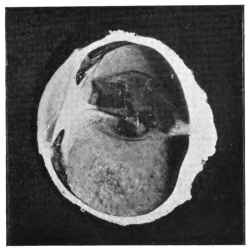

PLATE III.

16.

ABUNDANT EXUDATE INTO VITREOUS CAVITY

curly bracket span

42

17.

LENS FIRMLY FIXED BY ORGANIZED EXUDATE

18.

LENS FIRMLY FIXED BY ORGANIZED EXUDATE, BUT IN UNUSUAL POSITION

19.

TOTAL DETACHMENT OF RETINA, WITH CYST FORMATION

20.

RECLINED LENS LYING IN FRONT OF THE HYALOID BODY

21.

RECLINED LENS LYING IN FRONT OF THE HYALOID BODYxii